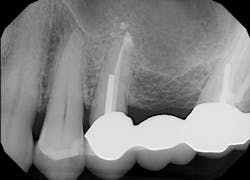

The patient, a 63-year-old female, presented for an emergency visit. She explained her situation, complaining of pain and a lump on the top-left quadrant of her mouth. After an oral evaluation and x-ray (figure 1), it was discovered that she had a large draining granuloma with swelling in the mucobuccal fold near teeth Nos. 12–14 due to a chronic periapical abscess (figure 2).

After using a round burnisher and blow test to determine that there was no perforation to the sinus and the membrane was still intact, the laser was used at a spot size of 1.25 mm, on low power mode, and without mist or air to debride the medial superior area of the bony defect. X-rays were taken following immediate placement of bone-graft material to display the site after using Solea to remove bone and granulation tissue (figures 6 and 7). The entire procedure, including the bone graft, took approximately 40 minutes from start to finish.